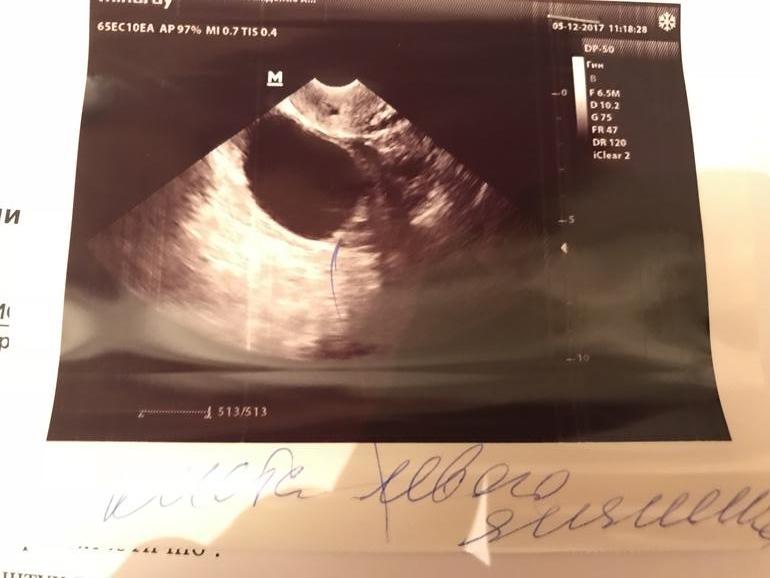

Сказать что я в шоке- ничего не сказать, кошмар! На этот цикл была большая надежда, ждала овуляцию , делала тесты, решила сходить и посмотреть что там , а там киста , фолекул самый большой 1см , знаю что это очень мало для 12 дц.

Так вот в чем вопрос, разругал ли беременеть? Фото прилагаю